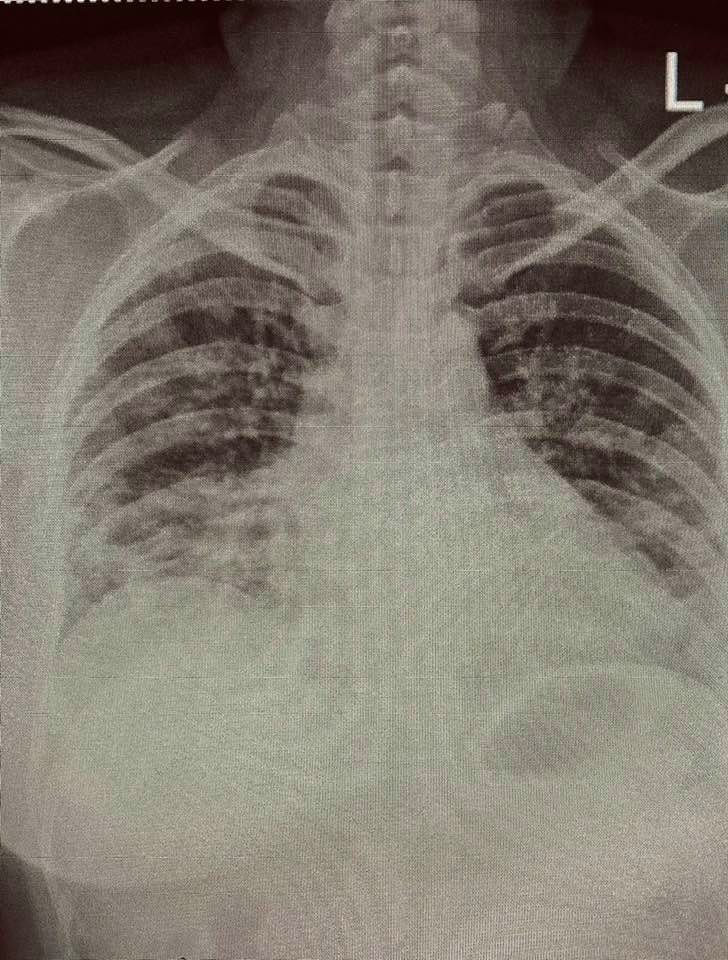

หมอจุฬาฯ เผย โควิดระลอกใหม่ เชื้อดุกว่าเดิม วัยรุ่นแข็งแรงก็ปอดอักเสบ

2. รอบก่อนๆ ไม่ค่อยเห็นวัยรุ่นที่สุขภาพแข็งแรงเกิดปอดอักเสบ แต่รอบนี้พบมากขึ้นกว่าเดิม

3. หลังจากที่ติดเชื้อไปแล้วประมาณ 1 สัปดาห์ คนที่มีความเสี่ยงเกิดอาการรุนแรงจะเริ่มมีอาการให้เห็น แต่รอบนี้เร็วกว่าเดิม ไม่ถึงสัปดาห์ก็เริ่มมีอาการมากขึ้น การอักเสบเกิดขึ้นเร็ว การให้ยาต้านไวรัสกับยาสเตียรอยด์ต้องพร้อม การวินิจฉัยปอดอักเสบต้องทำได้เร็ว